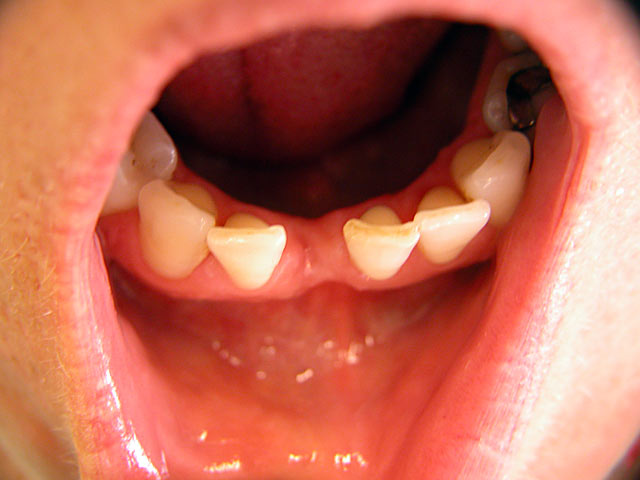

Die folgenden Patientenfälle sollen Ihnen einen Einblick in die Möglichkeiten der modernen Implantation geben.

Implantation – Patientenbeispiel 1: